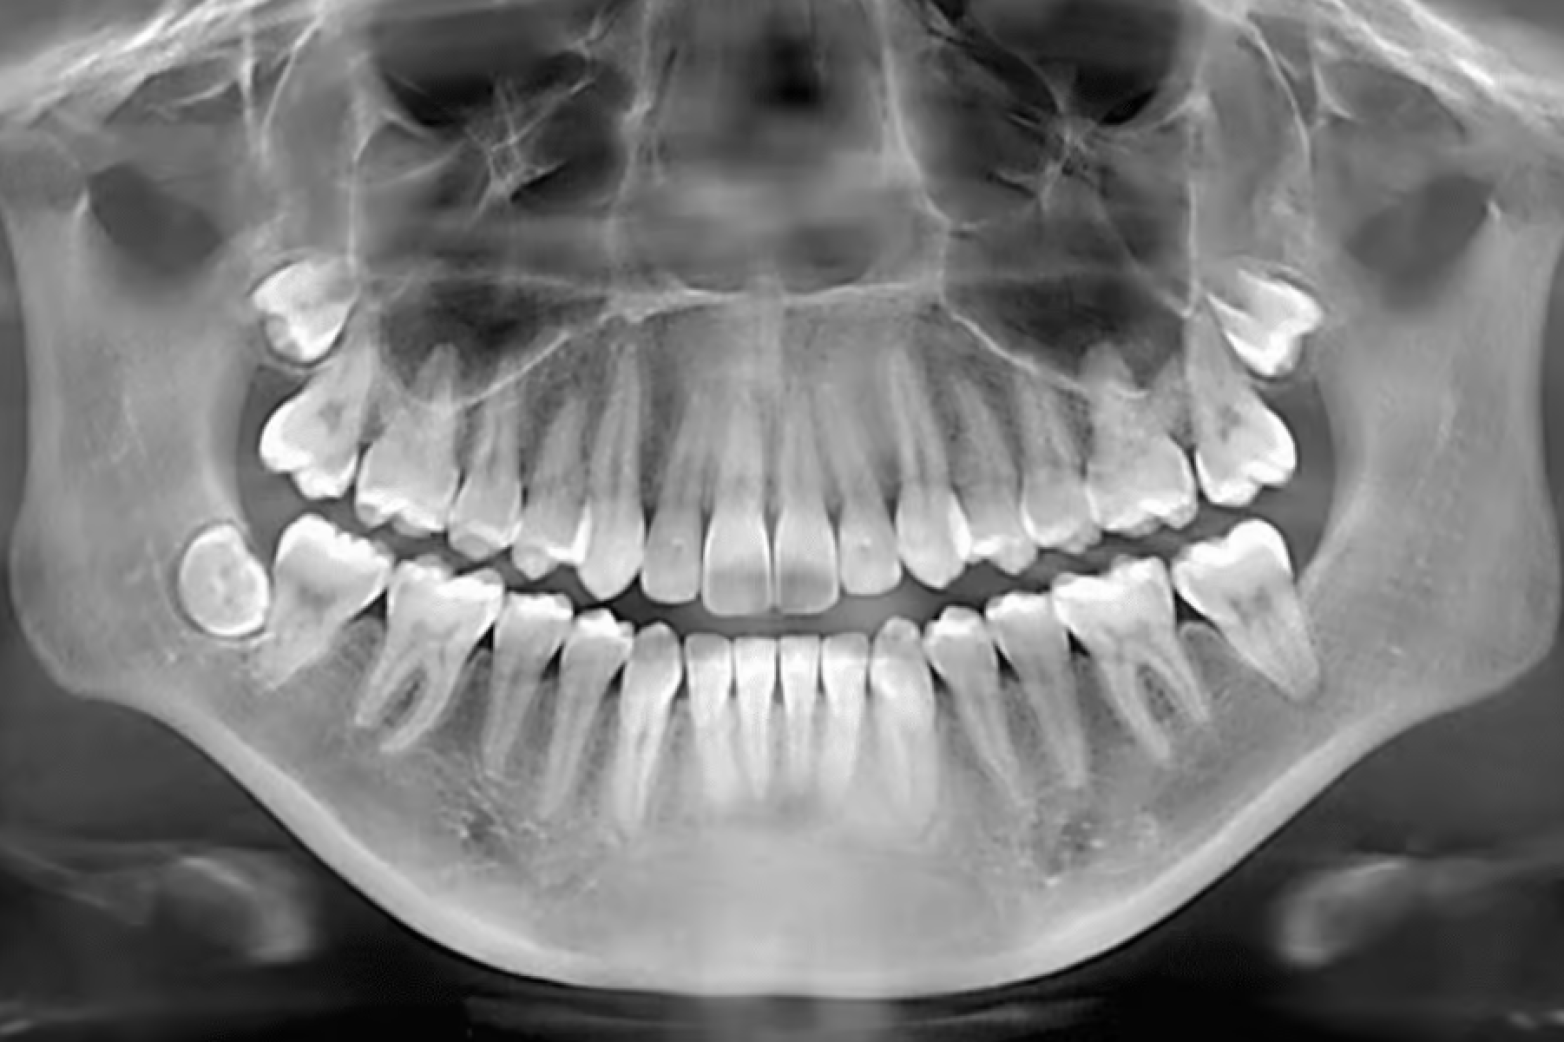

Dental X-rays help reveal problems that cannot be seen with the naked eye. They allow dentists to look inside the teeth, below the gums, and around the jawbone. These images help detect issues early before they become serious.

Your mouth has many areas that are hidden during a regular dental check-up. The spaces between teeth, the roots beneath the gums, and the bone that supports your teeth cannot be fully examined without imaging.

Dental X-rays create detailed pictures of these areas. They help dentists identify small problems before symptoms appear.

One of the most common uses of dental X-rays is to detect cavities that form between teeth.

These cavities are often difficult to see during a normal exam. Even careful inspection may not reveal them because they develop in tight spaces.

X-rays allow dentists to see these areas clearly. Dark spots on the image may indicate tooth decay between teeth.

Healthy teeth depend on strong bone support. The jawbone holds the tooth roots in place and keeps them stable.

Dental X-rays help measure the level of bone around each tooth. If bone loss begins, it may be a sign of gum disease.

Early bone loss is not always visible during a normal examination. But X-rays can reveal subtle changes in bone levels.

Dental X-rays are also useful for tracking how teeth develop over time.

In children and teenagers, X-rays show how permanent teeth are forming beneath the gums. They help dentists monitor whether teeth are developing normally.

Sometimes teeth may grow in the wrong direction or remain trapped under the gums. These are known as impacted teeth.

Wisdom teeth often develop later in life. In many cases, they do not have enough space to grow properly.

Dental X-rays show the exact position of wisdom teeth within the jaw. They help dentists determine whether the teeth are growing normally or becoming impacted.

Impacted wisdom teeth can cause pain, infection, or damage to neighbouring teeth.